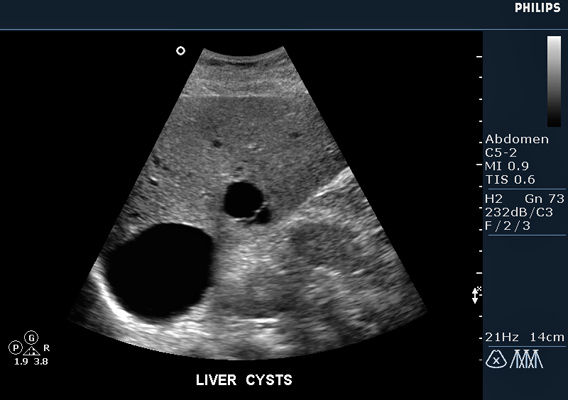

Normal Sonographic Anatomy 29 Figure 2-7 Hepatic veins. A transverse sonogram showing right (2),middle (3),and left (4) • Complex cyst may mimic tumor. Polycystic Liver Disease • Multiple anechoic masses with posterior enhancement (Figure 2-18) • May have low level echoes (debris) ... Retrieve Content

Liver Cysts And Abscesses - M.patient.media

Liver Cysts and Abscesses Liver cysts Epidemiology Hepatic cysts are usually asymptomatic and are often found incidentally. Investigations: ultrasound, MRI and CT scanning can show cyst anatomy. LFTs may be mildly abnormal.[4] Treatment: ... Retrieve Document